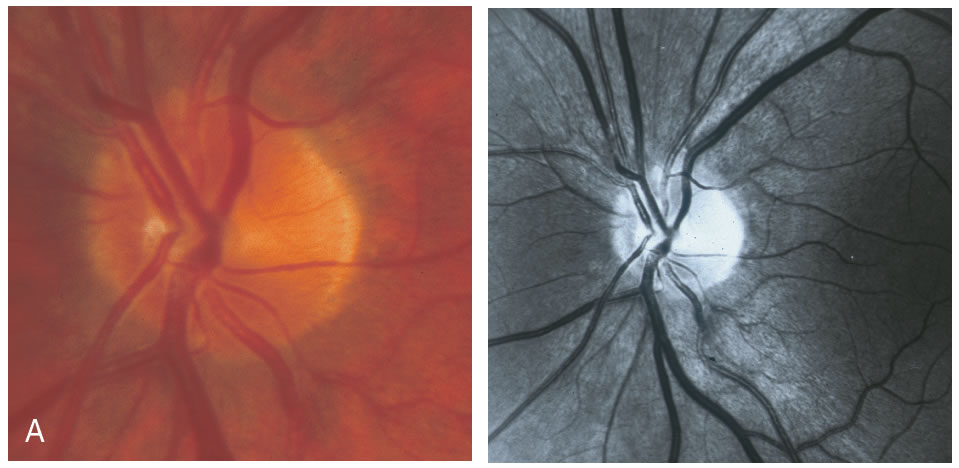

To evaluate the topographic information a contour line defining the disc margin is drawn by the examiner around the inner margin of the peripapillary scleral ring. The HRT software then establishes a reference plane 50 μm posterior to the retinal surface at the papillomacular bundle. The reference plane is established at this location because the fibers in the papillomacular bundle are thought to be least affected as glaucoma progresses, thereby providing a stable reference plane. As displayed in Figure 3, all structures below the reference plane are considered to belong to the optic cup (red) and all structures above the reference plane and within the contour line are considered to belong to neural rim (blue).

Stereometric parameters of optic nerve head topography are generated relative to the reference plane and include rim area, rim volume, cup area, cup volume, cup-to-disc ratio, mean RNFL thickness, and RNFL cross-sectional area. Parameters independent of the reference plane include mean and maximum cup depth, height variation contour, and cup shape measure (the statistical third moment of the distribution of all cup depth measurements). A characteristic sign in normal discs is the configuration of the contour line height display that demonstrates a double hump pattern corresponding to the thicker distribution of nerve fibers along the superior and inferior poles of the ONH (Fig. 4). Glaucomatous structural damage is characterized by a reduction of parameters that describe rim structures (area, volume) and indicate tissue loss (cup shape measure, cup volume, cup-to-disc ratio, cup steepness). As shown in Figure 5, glaucomatous alterations are typically associated with an asymmetrical or diffuse flattening of the contour line, or localized depressions corresponding to disc notches.